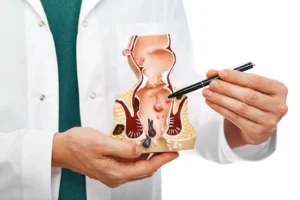

ما هي الأمراض الشرجية وكيفية الوقاية منها؟ الشرج هو جزء من الأمعاء البشرية التي تمر عبر تجويف الحوض و العضلة العاصرة الشرجية. في الواقع، هناك

سرطان المستقيم هو نوع من السرطان ينشأ على هيئة نمو للخلايا في المستقيم. ويوجد المستقيم في آخر الأمعاء الغليظة بطول عدة سنتيمترات. حيث يبدأ المستقيم